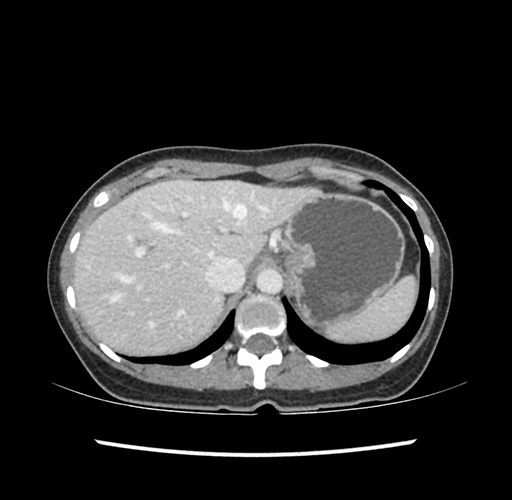

Imaging Analysis

Look through the patient's CT scan to identify any areas of concern for the necessary procedure.

Based on your CT findings, which issue(s) would give reason for "planned slowing down moment(s)" in this case?